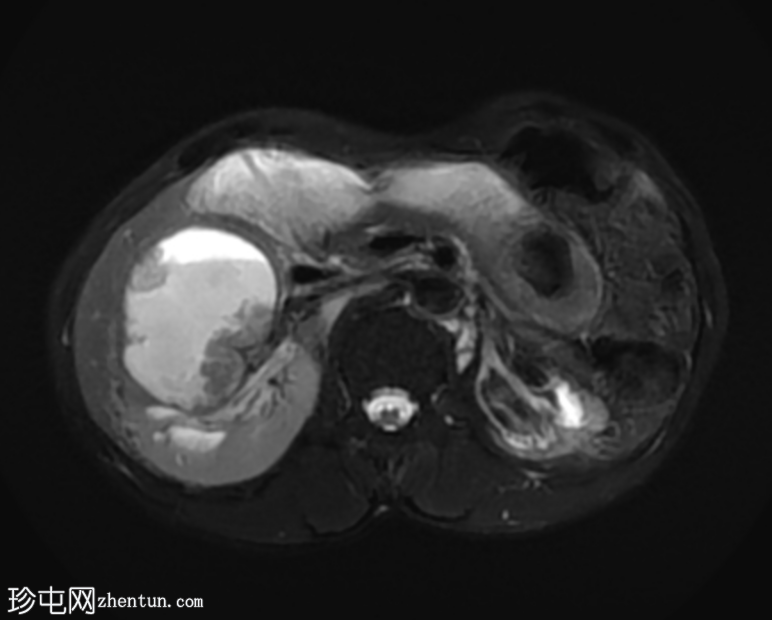

MRI

4.png

冠状位

T2加权像

再次观察到上述肾前部外生性病变,其实性成分在T1加权像上呈等高信号,在T2加权像上呈低信号,伴有碎片扩散受限和低ADC值(化脓性物质)。囊性成分内部可见液-碎片/脓液界面。可见内部低信号结石。可见肾周模糊影。该病变压迫并可能侵犯右肾盂,导致中度肾积水。

病灶不规则的低信号,以及液-液界面伴有碎屑(可能为化脓性物质)扩散受限和肾周模糊,再次高度提示炎症性病变(黄色肉芽肿性肾盂肾炎,XGP),而非可能性较小的肿瘤。